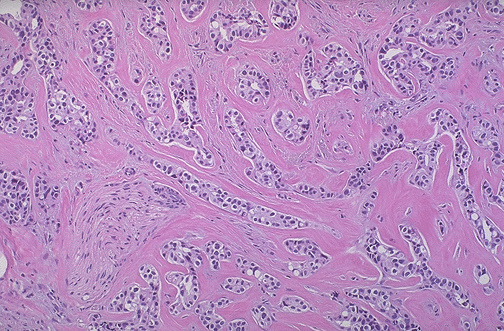

| Note the small nests and infiltrating strands of neoplastic cells with prominent bands of collagen between them in this ductal carcinoma of the breast. It is this marked increase in the dense fibrous tissue stroma that produces the characteristic hard "scirrhous" appearance of the typical infiltrating ductal carcinoma. Note the nerve surrounded by the neoplasm at the lower left. |